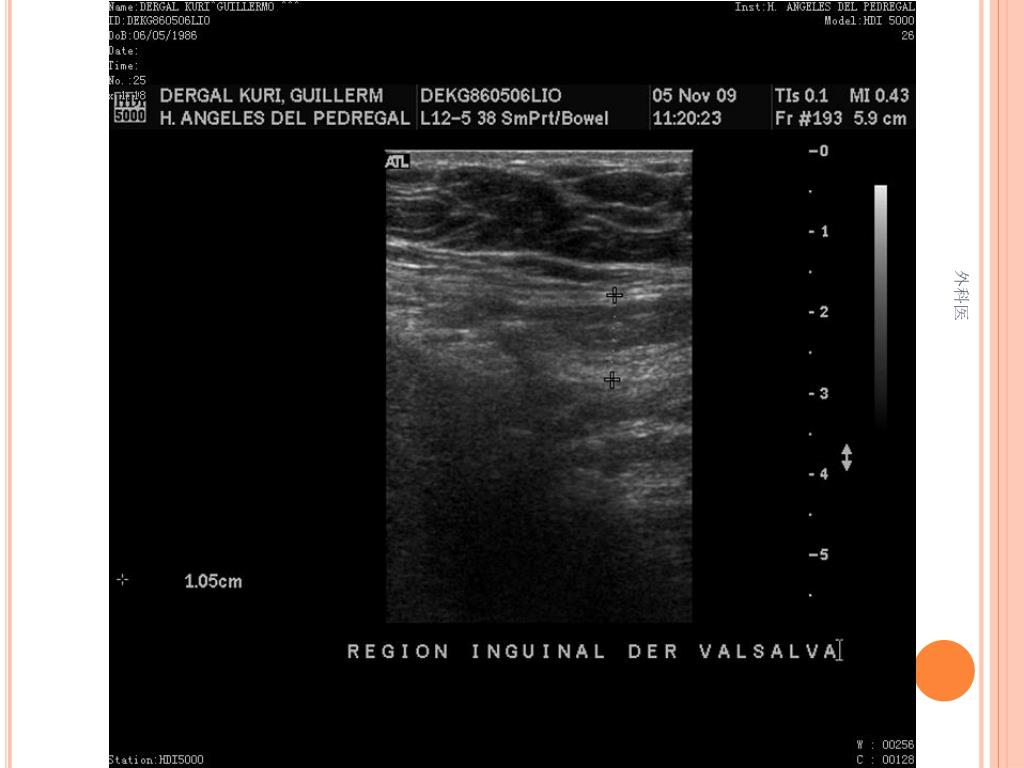

44. Tips • Leucocitos Mas de 20000/ml • Mas de 20% de la apéndices no se llenan con el bario por enema. • USG sensibilidad del 85% y Especificidad de mas 90% para Apendicitis Aguda. • TAC de Abdomen cortes de 5mm, sensibilidad y especificidad del 90% para dolor abdominal. • Analisis de 75000, taza de apendice negativa de 6% Hombres y 13% Mujeres 外科医